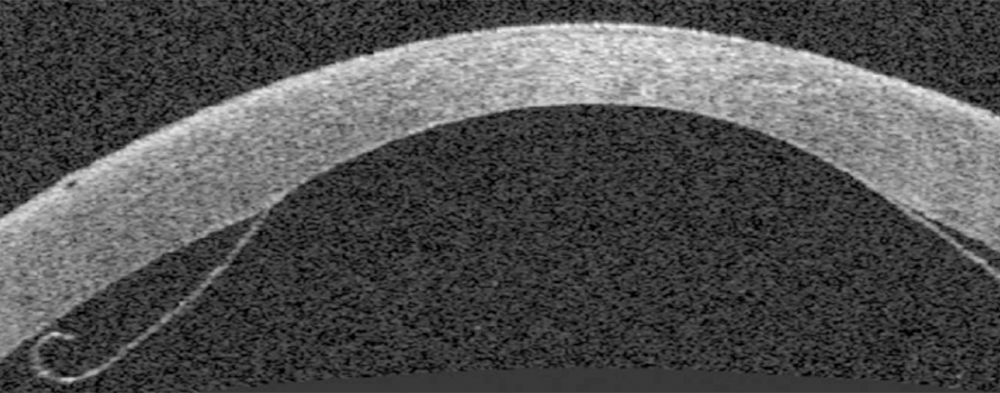

The next images show DSAEK and DMEK transplants. Notice how easy it is to see the DSAEK transplant in the eye, because it has a layer of stroma with it.  DMEK is almost impossible to see unless it is not fully attached yet.  This image of a partially separated DMEK is shown here just so that you can appreciate how thin the graft is when no stroma is transplanted.  You can see how important these grafts are to the cornea, because any area that doesn’t have the graft attached will swell thicker than other areas of the cornea.